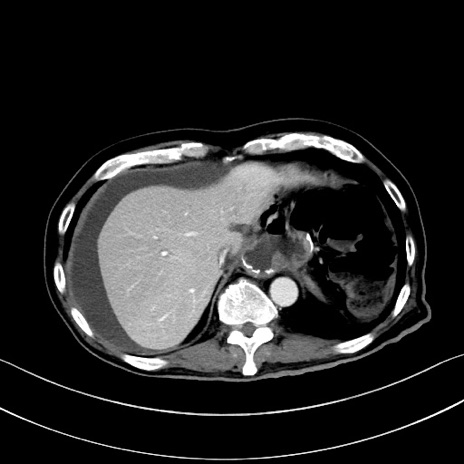

症例28(横断像)

【症例】60歳代男性

【主訴】嘔吐

【現病歴】胃癌にて胃全摘後。食思不振が悪化し、夜中に嘔吐することがある。

【既往歴】胃癌、胃全摘、脾摘、胆摘後

【データ】WBC 5900、CRP 10.56